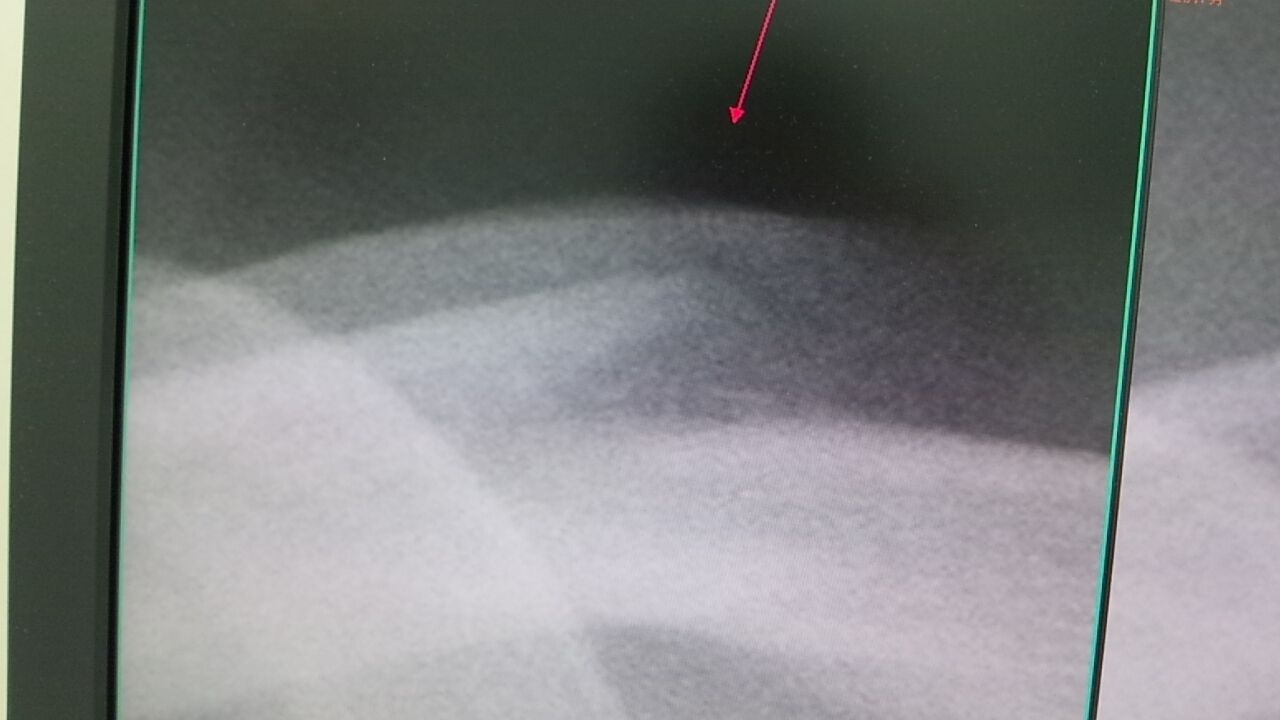

2013年07月13日 鎖骨骨折でも早期に参戦! . 昨年の全日本グランプリチャンピオン 鎖骨骨折後、2週間で骨癒合はじまり 3週間で競技参戦! スーパーテーピングを併用して、総合1位 びっくりです 彼の強いモチベーションを感じます。 . タグ :#練習用